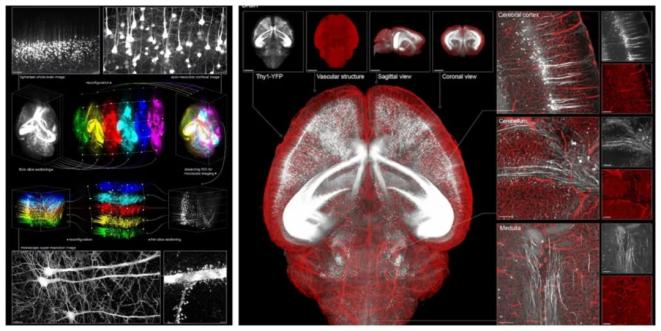

與此同時,配合團隊自研的三維重建算法TARRS,VIVIT還支持連續(xù)切片圖像的高精度拼接,可構建從單細胞到全器官的三維圖譜,實現(xiàn)跨尺度的結構還原。

VIVIT重構腦組織三維全景